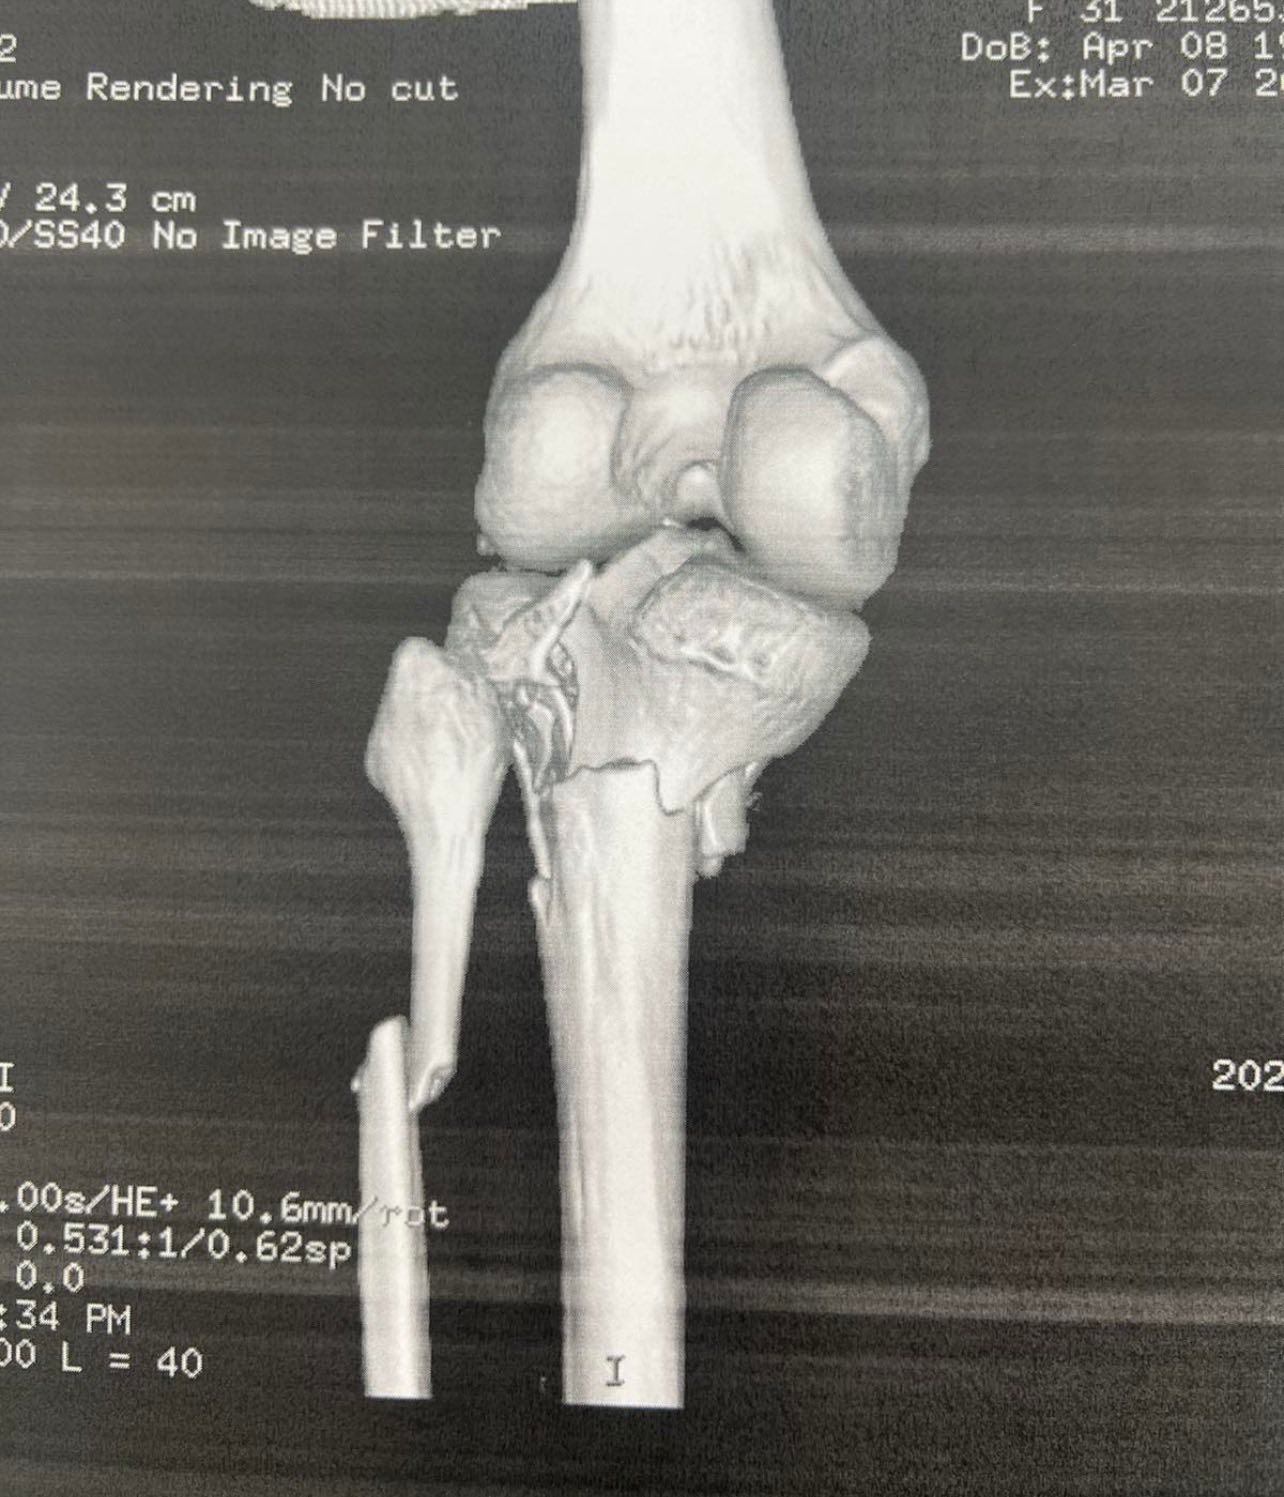

Μετά το χειρουργείο (αποτέλεσμα)

- Στόχος είναι η όσο γίνεται καλύτερη αποκατάσταση της αρθρικής επιφάνειας και της ευθυγράμμισης.

- Σημαντικό είναι και το κομμάτι της μετεγχειρητικής παρακολούθησης και φυσικοθεραπείας, με βάση τις οδηγίες του ιατρού.